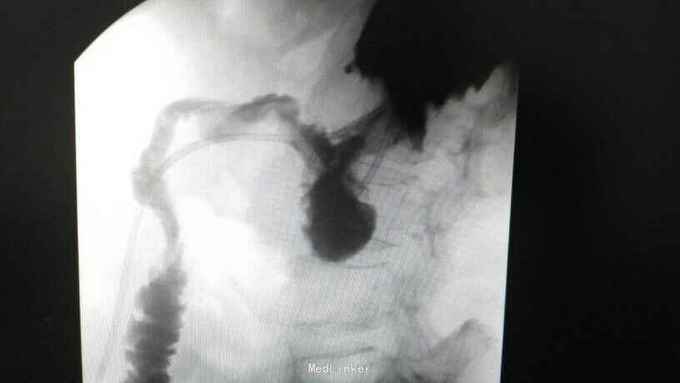

查体:入院后查体腹部平软,未见胃肠型,上腹部正中部可见20cm陈旧性瘢痕,腹部无压痛及跳痛,无肌卫;叩诊鼓音,肝脏及脾脏肋下未及;肝肾区无叩击痛,移动性浊音阴性,肠鸣音弱,1-2次/分。 检查:本次入院后查:WBC:9.2*10^9/L,Na:132mmol/L,余指标基本正常。电子胃镜:胃大部切除术后改变(毕II)吻合口粘膜充血水肿明显,直径约1.2cm,分别尝试进入输入袢及输出袢,见肠腔无明显狭;上腹部增强CT:1胰十二指肠切除术后;2肝脏多发小囊肿;3腹腔内未见明显感染及肿瘤转移征象。上消化道造影:残胃形态、扩张可,未见明显潴留液,蠕动较弱,中远部充盈不佳,胃小肠吻合口宽约1.2cm,未见狭窄及碘水渗漏。胃排空较慢。